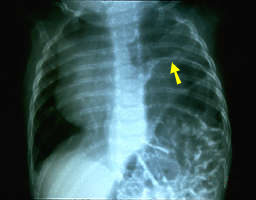

O nervo frênico controla o diafragma que se move com a respiração. O diafragma paralisado causa dificuldade respiratória, movimentos assimétricos do tórax durante a respiração, além de frequentes infecções pulmonares.

Esta radiografia de tórax mostra um deslocamento importante, para cima, do diafragma, distante do nível normal; vêem-se os intestinos na cavidade torácica. A paralisia do diafragma pode se resolver espontaneamente, exigindo, porém, atenção especial porque pode causar a morte. Como alternativas terapêuticas da lesão do nervo frênico temos a plication, na qual o cirurgião torácico faz o pregueamento do diafragma e o enxerto nervoso no nervo frênico.